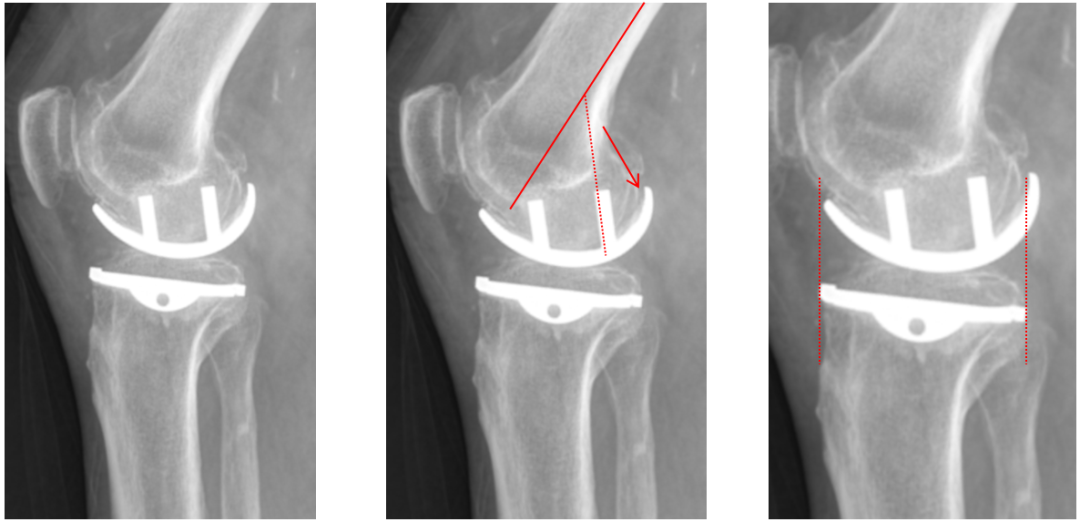

正位片标准胫骨和股骨假体位置

AP位假体位置:胫骨假体轻度外翻,外侧缘与胫骨平台外侧缘齐平; 股骨假体长轴与胫骨假体垂直,与胫骨假体中线一致。

侧位片标准胫骨和股骨假体位置

侧位片假体位置:股骨假体后倾38°,假体后缘与股骨后髁齐平,胫骨假体后倾3°,与胫骨平台前后缘齐平。

胫骨假体厚度合适

胫骨垫片厚度合适:术前外翻畸形基本矫正,残留2-3°外翻

胫骨假体后倾角度大

侧位片胫骨假体位置:胫骨假体后倾15°,前后缘齐平。

股骨假体偏小

侧位片股骨假体位置:股骨假体偏小,与胫骨假体后缘不齐平;屈曲35°,未包容股骨后髁。

股骨假体偏内放置

AP位胫骨与股骨假体位置:股骨假体中轴线与胫骨假体中线不一致,偏内侧,且外翻。

股骨假体偏外放置

AP位胫骨与股骨假体位置:股骨假体中轴线与胫骨假体中线不一致,偏外侧,且内翻